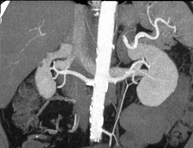

- Angio-TC arterias renales

Prueba diagnóstica no invasiva que consiste en el estudio de las arterias renales obteniendo imágenes de alta definición anatómica mediante el empleo de un equipo de TC (Tomografía Computarizada) y de contraste yodado. La calidad de las imágenes permite realizar reconstrucciones en 2D y 3D gracias a estaciones de trabajo especializadas en el estudio arterial. Esta prueba está indicada, por ejemplo, en aquellos pacientes que sufren de HTA refractaria al tratamiento, en pacientes con lesiones renales para tener un mapa "vascular" pre-quirúrgico, etc.